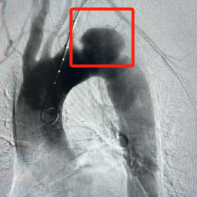

在放射介入治疗科、超声科、麻醉科、普外科、重症医学科等多学科协作支持下,放射介入治疗科张余副主任为患者进行了降主动脉覆膜支架腔内隔绝术。

支架的精准定位释放也十分重要。患者的降主动脉瘤距离左锁骨下动脉非常近,支架过高则影响左锁骨下动脉的血流,支架过低则不能实现良好的隔绝效果。术中凭借多角度造影及精湛的技术,支架释放精确,实现了“两全”。